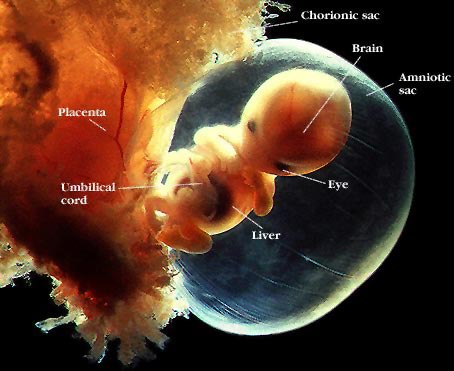

Незважаючи на те, що ваш малюк ще дуже маленький, він вже схожий на чоловічка: при УЗД на цьому терміні вже можна чітко розрізнити його головку і тулуб, розміри яких зараз майже однакові, ручки і ніжки, очі, початківці розвиватися вушка.

Темпи розвитку ембріона зараз просто вражаючі: щодня з ним відбуваються життєво важливі зміни. Його органи починають активно працювати, він отримує харчування через пуповину. На 8 тижні вагітності розмір малюка наближений до виноградині: його вага - близько 3 г, а зріст - 1,5 - 2 сантиметри.

Ембріон на 8 тижні вагітності і його розвиток

Триває розвиток ембріона. Минулого тижня його головний мозок вже розділився на три основні відділи, зараз відбувається їх вдосконалення.

Термін 7-8 тижнів вагітності характеризується формуванням пальчиків на ручках і ніжках малюка. У ембріона ще є хвостик, він поступово починає зникати.

Відбуваються зміни і в черевній порожнині ембріона. Починається формування кишечника. Середня його частина зміщується в пуповину, оскільки в черевній порожнині для неї поки недостатньо місця. Лише через місяць, коли черевна порожнина стане більш місткою, в неї повернеться частина кишечника, яка зараз розташовується в пуповині.

Активно формується і периферична нервова система малюка. Вже є іннервація деяких м'язів. Якби ви могли доторкнутися до бичка малюка, ви б відчули різкий ривок у відповідь.

У ембріона вже практично сформувалася четирехкамерное серце. Воно вже посилає кров в великі судини. Розгалужується бронхи, формуються нирки. Добре розвинені зачатки статевих органів.

У малюка починають формуватися риси обличчя. Вже є очі, які поки щільно закриті століттями і знаходяться на бічних поверхнях голови. Формуються вушка, губи, можна розрізнити носик, який поки ще закритий.

Стінки ротової порожнини ембріона вже мають м'язову тканину, починається формування слинних залоз, сосочків мови.

Ручки і ніжки малюка вже можуть згинатися - формуються великі суглоби. Малюк вже може рухатися.